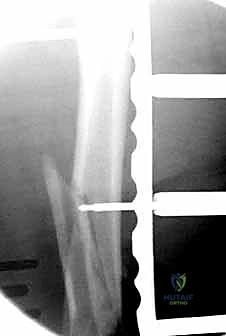

تُعد جراحة "الرد المفتوح والتثبيت الداخلي" (Open Reduction and Internal Fixation - ORIF) هي الإجراء الأكثر شيوعاً ونجاحاً. سنأخذكم في رحلة مفصلة داخل غرفة العمليات لنوضح كيف يقوم البروفيسور هطيف بإعادة بناء العظم بدقة هندسية.

المرحلة الرابعة: التثبيت النهائي بالشرائح والمسامير (Fixation)

يتم استخدام "شرائح الإغلاق التشريحية" (Anatomical Locking Plates) المصنوعة من التيتانيوم عالي الجودة. هذه الشرائح مصممة خصيصاً لتأخذ شكل الجزء السفلي من عظم الفخذ. يتم تمرير الشريحة أسفل العضلات وتثبيتها بمسامير تغلق داخل الشريحة نفسها (Locking Screws)، مما يوفر ثباتاً ميكانيكياً هائلاً، حتى في حالات العظام الهشة.

في بعض الحالات المعقدة جداً، قد يتطلب الأمر استخدام شريحتين (Dual Plating) لضمان عدم تحرك الكسر أثناء فترة التعافي.

بعد التأكد التام من استقرار الكسر وحركة المفصل عن طريق الأشعة داخل غرفة العمليات، يتم إغلاق الجرح بطبقات متعددة باستخدام خيوط تجميلية لتقليل الندبات، ووضع أنبوب تصريف (Drain) لمنع تجمع الدم.